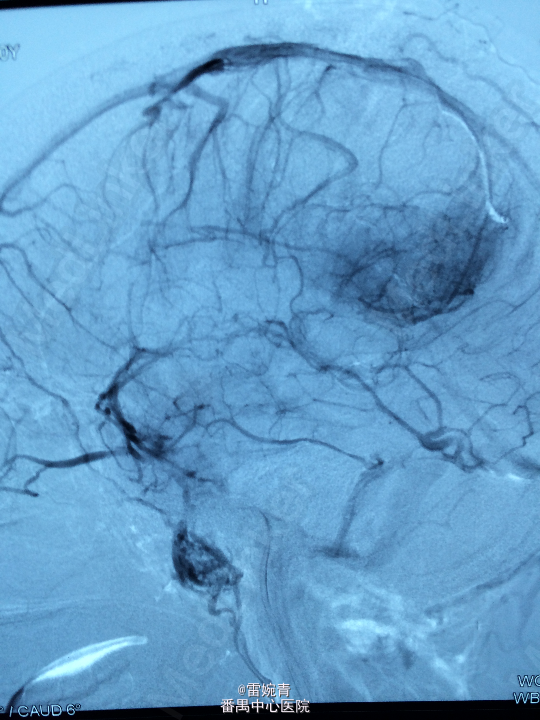

诊断:脑膜瘤 处理:先行DSA检查以明确脑膜瘤的供血动脉情况,见:肿瘤染色,肿瘤主要由左侧眼动脉供血,用Glubran胶将其闭塞,后择期行手术切除治疗。术后病理证实为脑膜瘤。

术后患者病情稳定,后出院。 讨论:脑膜瘤可由颈内颈外动脉双重动脉供血,血供较为丰富,直接开颅手术治疗出血量较多,如果能术前行介入栓塞治疗可减少书中出血量,并降低手术风险及难度。